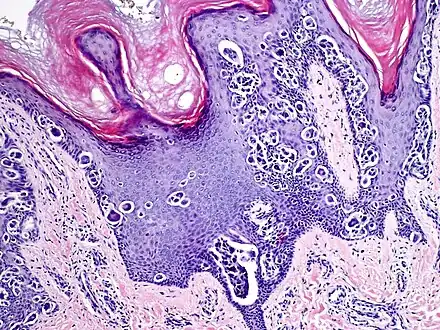

Melanocytic acral nevus with intraepidermal ascent cells (MANIAC)

They are brown to dark brown in color and have linear streaks of darker pigmentation. Size is usually 7 mm or less, oval or spindle shaped, and well-demarcated. They become stable after an initial growth phase, and the number of lesions also decreases; a new lesion in middle-aged or elderly people should raise suspicion of acral lentiginous melanoma.